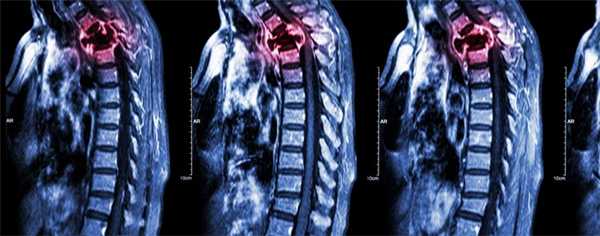

Компрессия спинного мозга

Компрессия спинного мозга выявляется у 1-5% пациентов с метастатическими поражениями позвоночника. В 70% случаев причиной нарушений становятся метастазы в грудные позвонки, в 20% - в поясничные и крестцовые позвонки, в 10% случаев – в шейные позвонки. При метастазах в кости могут выявляться как острые (при сдавлении костным фрагментом), так и постепенно прогрессирующие (при сдавлении растущей опухолью) расстройства. При сдавлении растущим новообразованием пациентов с метастазами в кости беспокоят нарастающие боли. Развивается мышечная слабость, выявляются нарушения чувствительности. На заключительной стадии возникают парезы, параличи и нарушения функции тазовых органов.

При сдавлении фрагментом кости клиническая картина компрессии спинного мозга развивается внезапно. На начальных стадиях оба вида компрессии обратимы (полностью или частично). При отсутствии своевременной медицинской помощи в течение нескольких часов или дней паралич становится необратимым. Своевременное адекватное лечение позволяет уменьшить выраженность симптомов, однако восстановление способности к самостоятельному передвижению отмечается всего у 10% больных с уже развившимся параличом.